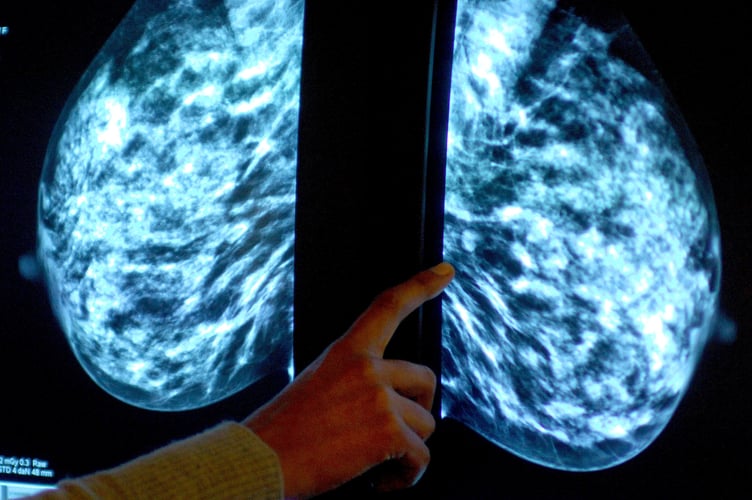

Breast screening uptake in Cornwall remains below pre-pandemic levels, new figures show.

Anyone registered with a GP as female will be invited for NHS breast screening every three years between the ages of 50 and 71.

NHS England figures show 23,810 of the 35,080 people invited for a screening in the former NHS Kernow CCG had a test in the year to March this year.

It meant uptake of the screening stood at 68% – up from 67% the year before, but below pre-pandemic levels of 74% in 2019-20.